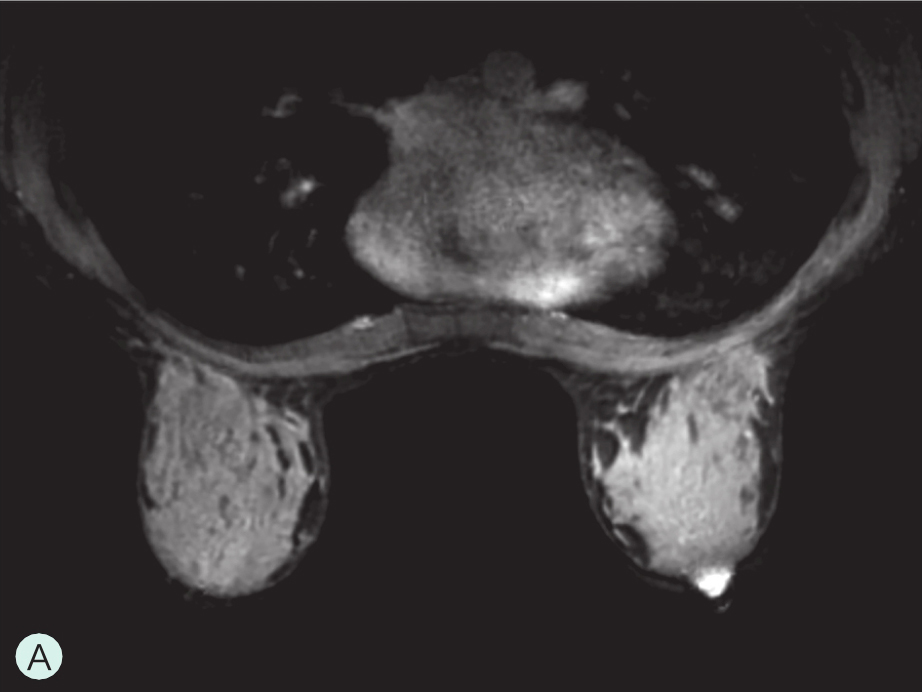

乳腺主要由胸廓内动脉、胸外侧动脉及肋间穿支动脉供血(图1-4-1A~图1-4-1C)。胸廓内动脉发自锁骨下动脉,在相应肋间胸骨旁发出分支穿过胸大肌,主要供应乳房的内侧部分血供;胸外侧动脉发自腋动脉第2段,穿过腋静脉深面,经腋窝沿胸小肌下缘走行,负责胸大肌、胸小肌、前锯肌及乳房外侧部分血供;另外,第3~5肋间动脉从各相应的肋间穿出,与胸外侧动脉及胸廓内动脉分支吻合,供应乳房下部分血供。上述三组主要动脉在乳房内又不断分支并相互吻合形成血管网,且走行自然连续,但缺乏类似于肝脏及肾脏有规律的血管分支树结构,同一女性双侧乳房或不同女性间都不相同,无固定分支规律可循(图1-4-1D)。

图1-4-1 乳腺血供与影像学

A.乳腺血供示意图;B.乳腺增强MRI造影血管图;C.乳腺增强MRI三维重建血管图;D.乳腺血管铸型解剖标本

1.胸廓内动脉;2.腋动脉;3.胸外侧动脉